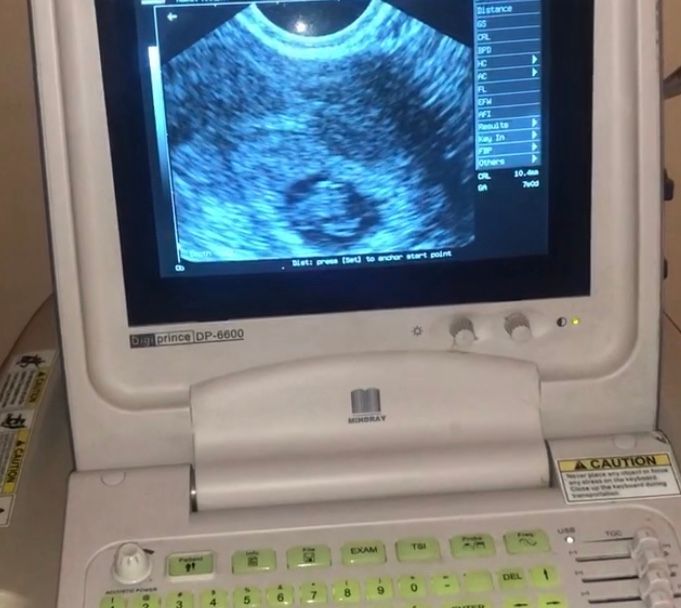

Снимок УЗИ на 7 неделе

Девочки мой срок на этом фото 7 недель и 4 дня. Это хороший снимок ???!!кто опытный в этом плане подскажите🤱🏻🙏🏼🙏🏼Мне не понравилось лицо врача, она была какая то сомнительная, но мне сказала что все там отлично! Посоветуйте ((

Как по мне так некачественный снимок....ничего не понятно🤷♀️ И если врач сказал,что всё отлично, то не переживайте!! Лёгкой беременности Вам))